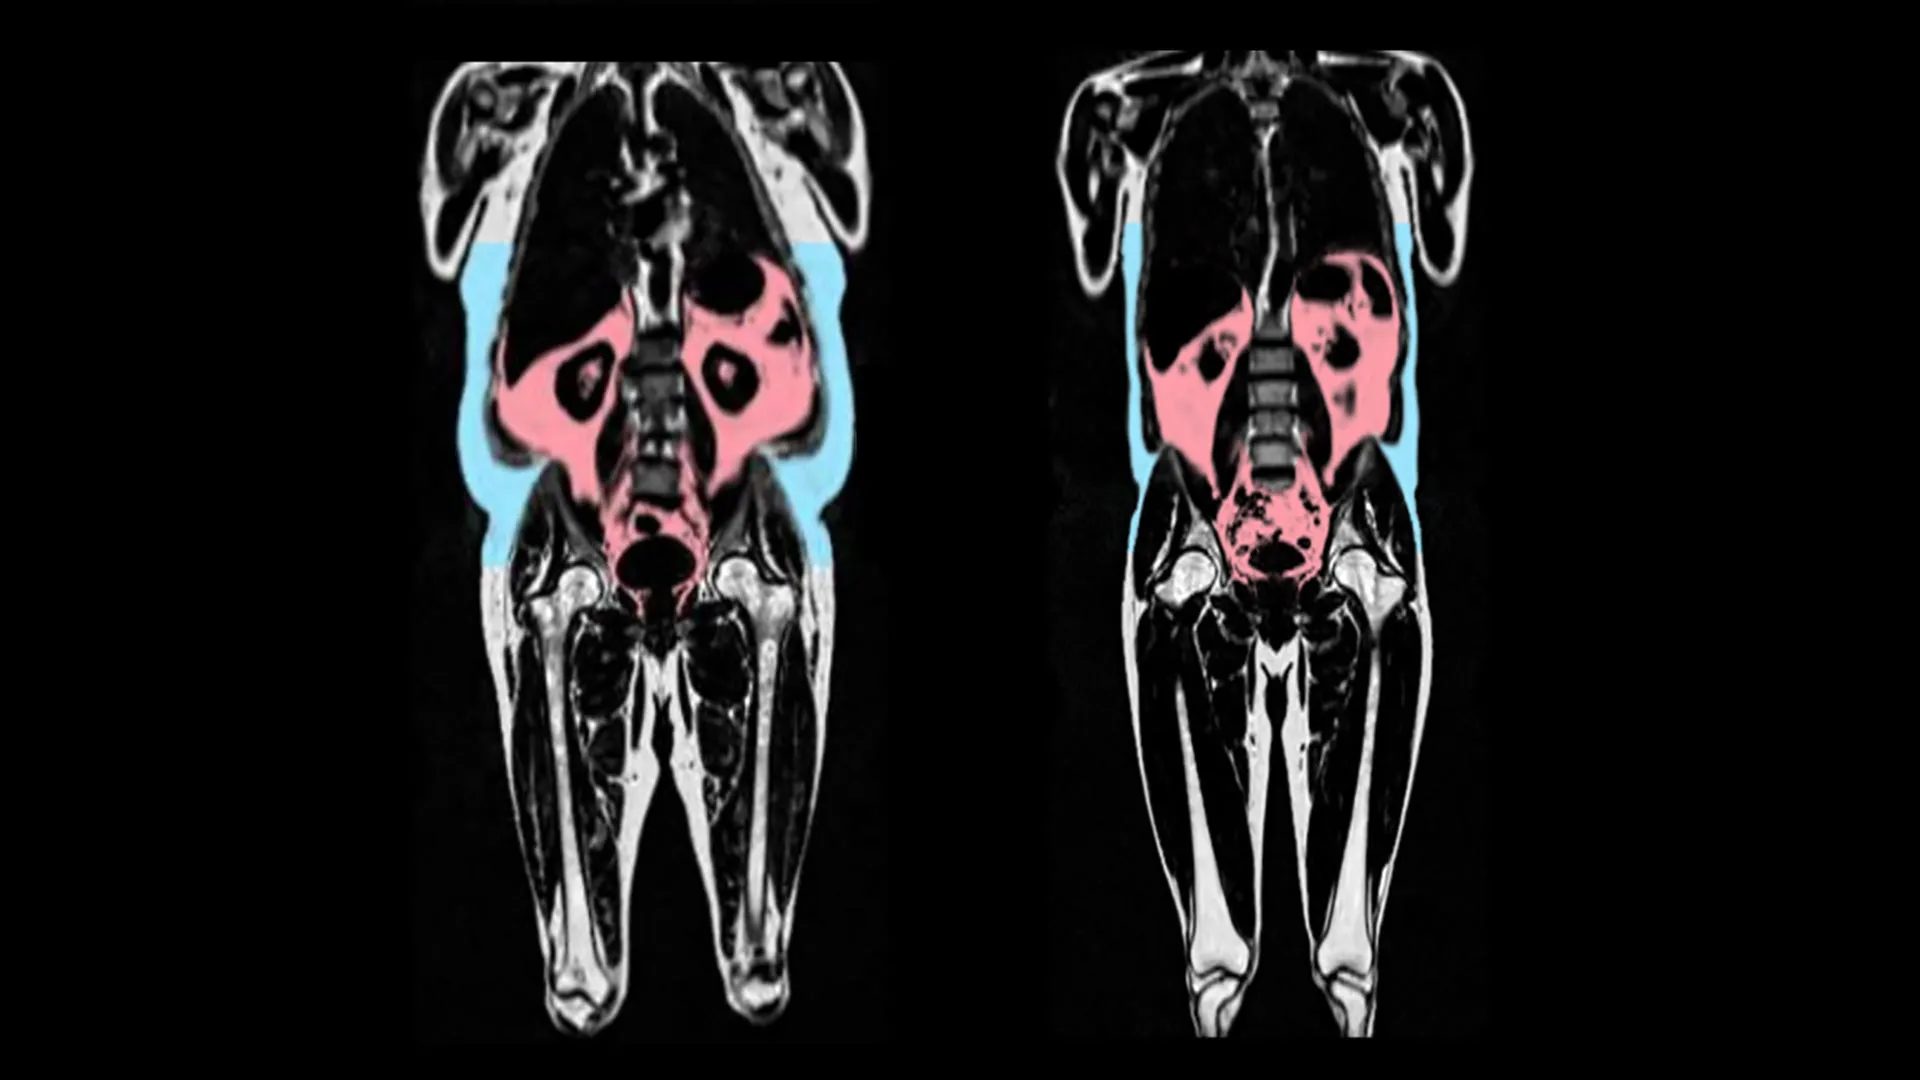

Within the research, printed within the European Coronary heart Journal, the scientists analyzed information from 21,241 individuals in UK Biobank, which incorporates complete physique imaging to map the quantity of fats and the place it’s situated within the physique.

The UK Biobank information additionally consists of detailed imaging of the center and blood vessels. Synthetic intelligence was used to analyse these photographs to seize indicators of organ getting older — similar to tissues turning into stiff and infected. A person was given a “coronary heart age” which may be in comparison with their precise age on the time of the scan.

The researchers discovered that quicker coronary heart getting older was linked to having extra visceral adipose tissue. Visceral adipose tissue is fats discovered deep contained in the stomach round organs such because the abdomen, intestines, and liver. Such a fats can’t be seen from the skin, and a few folks can have giant quantities of visceral fats regardless of having a wholesome weight.

Additionally they discovered variations between the sexes. Male-type fats distribution (fats across the stomach, typically known as ‘apple’ formed) was significantly predictive of early getting older in males.

In distinction, a genetic predisposition to female-type fats (fats on the hips and thighs, typically known as “pear” formed) was protecting towards coronary heart getting older in girls.

Professor Declan O’Regan, who led the analysis on the MRC Laboratory of Medical Sciences and Imperial Faculty London, and is the British Coronary heart Basis Professor of Cardiovascular AI, stated: “We have now recognized in regards to the apple and pear distinction in physique fats, but it surely hasn’t been clear howit results in poor well being outcomes. Our analysis reveals that “dangerous” fats, hidden deep across the organs, accelerates getting older of the center. However some forms of fats may shield towards aging- particularly fats across the hips and thighs in girls.”